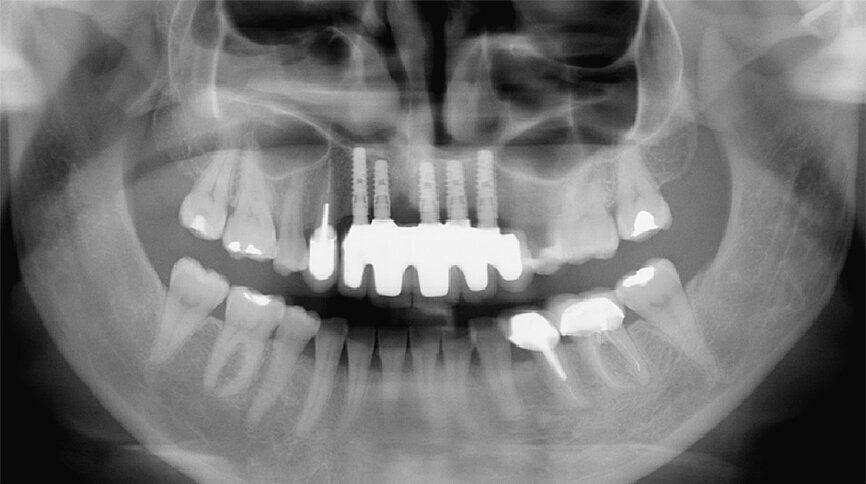

Fig. 40: Radiographic check-up after seven years.

In the following step, the final prosthesis was installed and the correct occlusion verified: maximum intercuspation, protrusion and lateral excursion. The screw channels were filled with composite (Figs. 36 & 37).

The final cosmetic check-up, validated by the resin prosthesis, showed the lip support with the new extremely reduced false gingiva to be correct (Figs. 38 & 39). This was achieved owing to the bone graft.

Regular check-ups

Retreatment was regularly monitored with patient check-ups (Fig. 40). All implant treatments, no matter of what type, must be rigorously monitored in all treatment phases, but a retreatment requires even more diligence. A patient affected by the failure of a previous treatment will not accept even the smallest problem. To this end, the role of healing periods is thus essential to retreatment success.